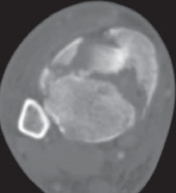

22.

Cole et al3 mapped 38 consecutive AO/OTA 43-C3 (complex articular) plafond fractures with CT scans and found that all plafond fractures in this category exited the tibiofibular joint laterally and at two separate locations medially to create a coronally oriented Y pattern with three major fragments ( FIG 2A). There were also varying amounts of articular comminution anterolaterally or anteromedially (FIG 2B).

--- A B ### FIG 2 • A,B. CT images from 43-C3 plafond injuries demonstrating typical fracture patterns with anterolateral, medial malleolus, and posteromedial fragments. Variable amounts of central or anterocentral articular impaction and comminution are commonly seen.